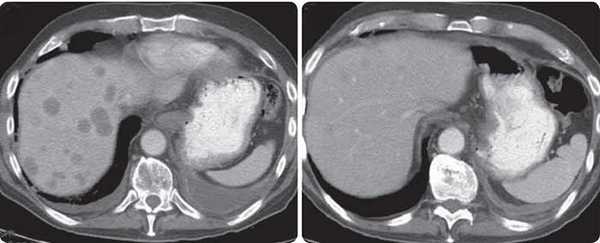

При подозрении на рак поджелудочной железы врач в первую очередь, скорее всего, назначит компьютерную томографию. На снимках хорошо видна поджелудочная железа, можно обнаружить не только первичную опухоль, но и ее распространение в соседние органы, отдаленные метастазы. Кроме того, КТ позволяет оценить возможность хирургического лечения.

Наиболее информативна многосрезовая компьютерная томография (МСКТ) с многофазным внутривенным болюсным контрастированием. Во время этого исследования снимки выполняют спустя определенные промежутки времени после внутривенного введения контрастных растворов.

Современные ультразвуковые аппараты позволяют уточнить локализацию опухоли, ее размеры и взаимоотношение с крупными сосудами брюшной полости. Однако, более точное расположение опухоли, наличие отдаленных метастазов, вовлечение в опухолевый процесс сосудов брюшной полости позволяет оценить компьютерная томография органов брюшной полости с внутривенным контрастированием.